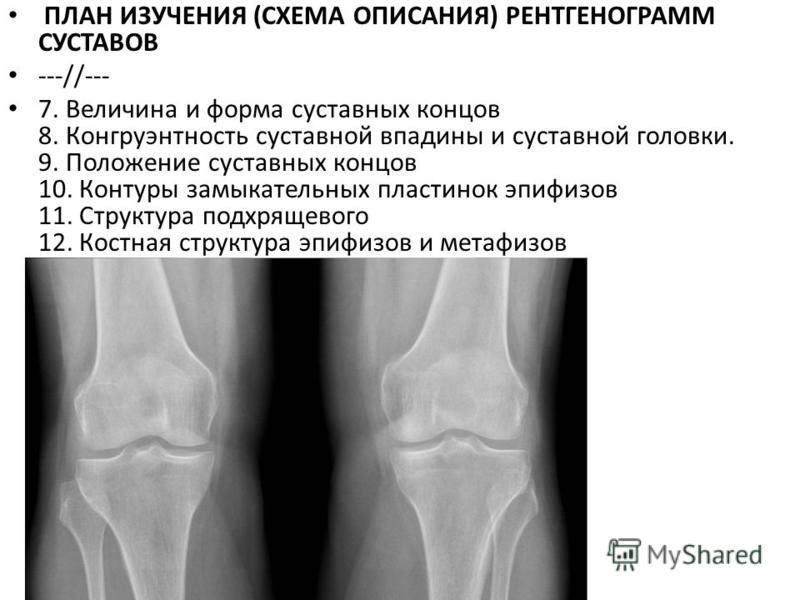

Медицинские снимки: рентген коленного сустава при остеопорозе